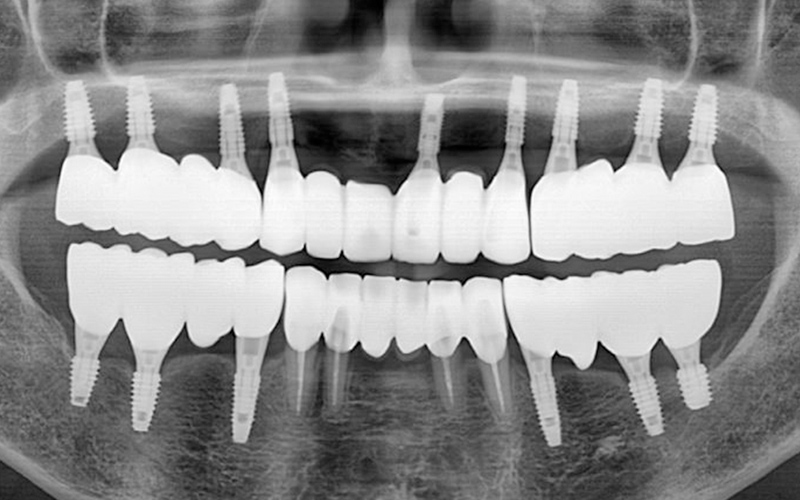

전악 임플란트는 임플란트 틀니보다 씹는 힘이 훨씬 좋습니다.

내 치아처럼 사용이 가능하며

전체 치아 기능의 90% 정도로 회복력이 좋습니다.

개인 치아 형태와 교합을 고려한

최종 보철물을 제작·장착합니다.